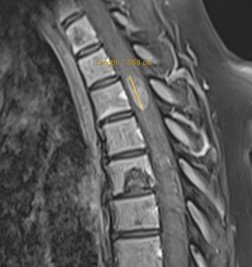

Pacientă în vârstă de 54 ani, cu un istoric îndelungat de neoplasm mamar, care acuză scăderea forței musculare în membrul inferior drept. RMN de coloană toracală a evidențiat o tumoră intramedulară T3-T4 de cca. 20/9/8 mm, centrală, relativ bine delimitată, care captează substanța de contrast – aspect sugestiv pentru o determinare secundară (metastază).

Intervenția chirurgicală a avut loc în bune condiții, reușind să extirpăm în cvasitotalitate țesutul tumoral fără a agrava pacienta din punct de vedere neurologic. RMN-ul de control efectuat a doua zi a confirmat absența rezecția completă precum și absența complicațiilor postoperatorii. Din punct de vedere neurologic, evoluția a fost favorabilă, cu ameliorarea treptată a deficitului motor sub kinetoterapie, pacienta putând fi mobilizată începând cu a doua zi postoperator, ulterior putându-și continua tratamentul oncologic: radioterapie spinală, apoi chimioterapie sistemică și interatecală.